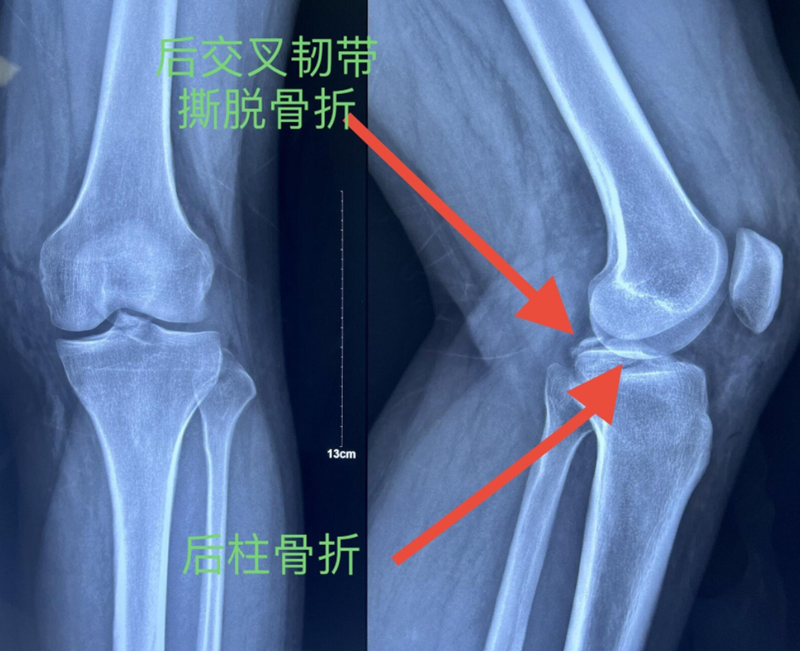

诊断:左胫骨平台后柱骨折,后交叉韧带撕脱骨折,左踝关节pilon骨折3型。

图7 前交叉韧带撕脱骨折与平台后柱骨折